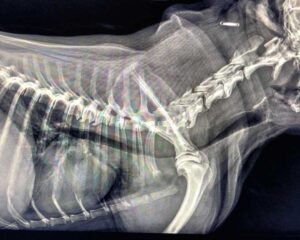

Zapadanie tchawicy u psów (TCS-Tracheal Collapse Syndrome)

Źródło: https://wetgliwice.pl/ Zapadanie tchawicy u psów (TCS-Tracheal Collapse Syndrome) Zapadanie tchawicy u psów (TCS-Tracheal Collapse Syndrome) jest przewlekłą chorobą układu oddechowego obserwowaną głównie u raz małych i miniaturowych (Yorkshire terrier, Szpic …